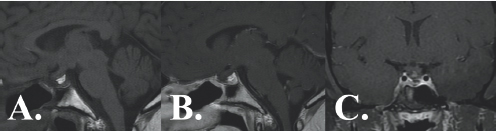

Three images show gray colored variations surrounded by black and white outlining.

FIGURE 7.4 Post-operative MRI demonstrates complete removal of the tumor with no evidence of returning growth.

Arianna and her doctors have been very pleased with her recovery after the surgery. MRIs obtained at six months (Figure 7.4), and twelve months following the operation have shown no evidence of residual or recurrent tumor. Arianna’s vision has been completely restored; all other symptoms have resolved under the care of the endocrinology team. She has been able to restart her hormone therapy regimen to reaffirm her identity as a transgender woman. After defeating struggles with identity, hormonal fluctuation, visual loss, and tumor removal, Arianna was ready to live life to its fullest.